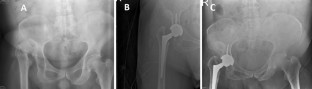

Fig. 1